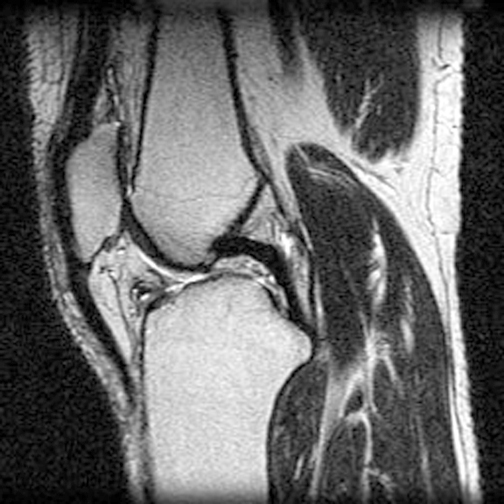

Identify the structures seen. Click the image for labeling.